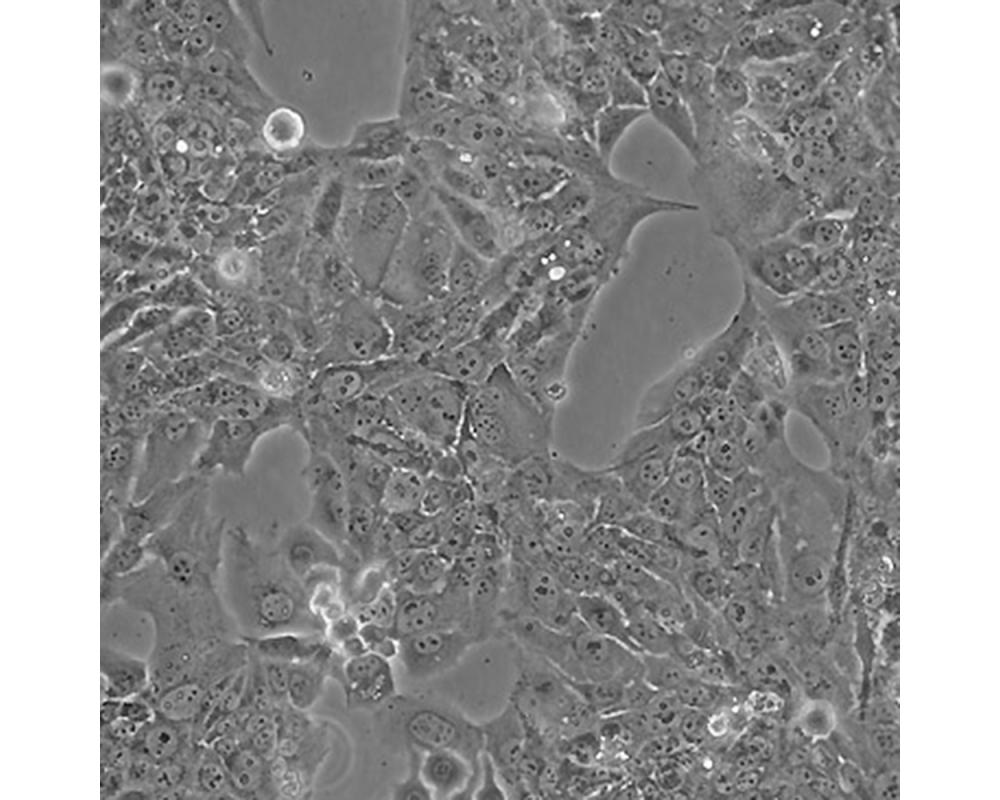

中文名稱 人胎盤絨膜癌細(xì)胞

組織來源 妊娠性絨癌

形態(tài)特征 上皮樣

生長特性 貼壁生長

特征特性 取自人絨癌腦轉(zhuǎn)移組織,在倉鼠頰囊移植傳代8年。利用移植瘤組織進(jìn)行體外培養(yǎng),建立細(xì)胞系。利用不同傳代方法建立了不同亞系,JEG-3是其衍生克隆。該細(xì)胞可以產(chǎn)生雌激素、孕激素、雌酮、雌二醇、雌三醇、hCG、胎盤催乳素、角蛋白。